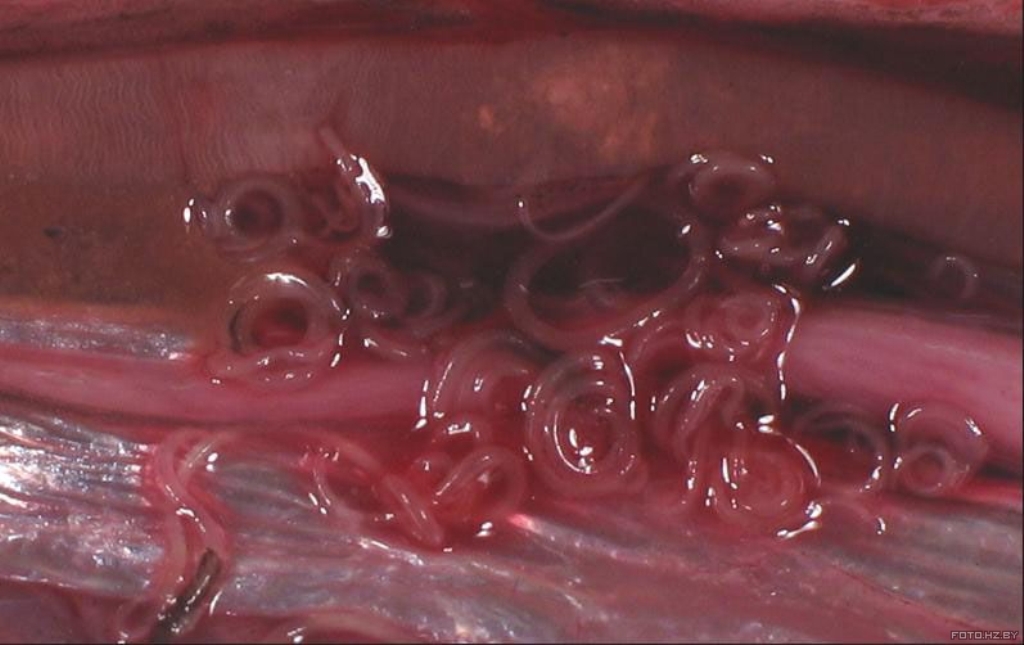

Анизакиоз

Анизакиоз. Возбудители анизакидоза человека – личиночные стадии развития гельминтов родов: Anisakis, Contracaecum, Pseudoterranova, Hysterothylacium, относящихся к отряду Ascaridida Skrjabin et Schikhobalova, семейству Anisakidae Skrjabin et Korokhin. Окончательными хозяевами этих гельминтов служат многие морские млекопитающие (китообразные, ластоногие), хищные морские рыбы и рыбоядные птицы, в желудочно-кишечном тракте которых паразитируют самцы и самки анизакид. Средняя длина самок 60-65 мм, самцов – 50-55 мм. Тело веретенообразное, суженное к обоим концам (более сужено к головному концу). На головном конце имеется три губы. В теле рыбы находятся чаще в состоянии “плоской свёрнутой спирали”. Могут находиться как в полостях тела так и в мышечной ткани.

Личинки круглых червей могут поражать почти все виды морских рыб: тресковые, окунёвые, лососёвые и др. В частности, поражённость сельдевых в Балтийском море – 30%, а в Северном море – 55–100%. Рискуют заболеть все, кто любит японские блюда, приготовленные из сырой рыбы. Личинки анизакид могут провоцировать развитие язвы кишечника, инкубационный период – от 4–6 часов до 7 дней.